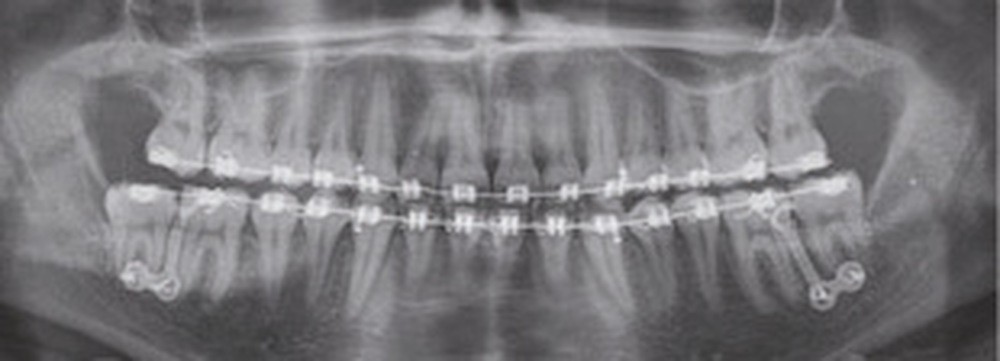

À la vue de l’examen radiographique, elle est au stade CS6 d’après la méthode de maturation vertébrale de Baccetti [1]. Elle présente une classe II squelettique de Ballard par rétrognathie mandibulaire avec un ANB de 9° et un AoBo de 9 mm sur un schéma facial normo-divergent. L’incisive mandibulaire est vestibulo-versée (IMPA = 114°). Le maxillaire est bien positionné. Elle présente de plus une dysharmonie dento-dentaire (DDD) antérieure par excès mandibulaire.

Nous équipons la patiente avec un appareil multi-attaches (.022 x .028 inch pré-informé Roth) mais nous n’avons pas activé l’arcade mandibulaire. La patiente est adressée au chirurgien maxillo-facial (Dr Gonzague Deffrennes, hôpital Beaujon) qui réalise l’avulsion des troisièmes molaires et la pose de plaques vissées avec émergence entre les premières et deuxièmes molaires mandibulaires dans l’axe des brackets (fig. 9). Étant donné l’absence d’encombrement au niveau incisif mandibulaire, nous pouvons rapidement mettre en place les tractions postérieures. Nous solidarisons ainsi le bloc antérieur de canine à canine et réalisons un recul en masse de l’arcade directement des canines aux plaques postérieures. La majeure partie du recul est faite sur un arc acier .018x.025 inch permettant le glissement. La force appliquée est de 250-300 g par côté.

Nous avons pu repositionner l’incisive mandibulaire de 8° (fig. 10), obtenir un surplomb correspondant à la classe II d’Angle et ainsi réaliser l’avancée mandibulaire. Le chirurgien accompagne celle-ci d’une génioplastie afin d’harmoniser le profil. Nous corrigeons la DDD par stripping des incisives mandibulaires ce qui permet de corriger encore de 1° l’axe incisif.